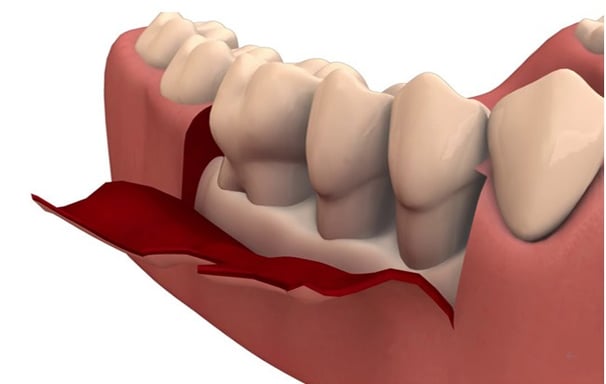

Es un procedimiento quirúrgico donde se levantan las encías para acceder a las raíces de los dientes y limpiar áreas profundas. Luego se reubican y se cosen las encías en su lugar para promover una mejor cicatrización.

Cirugía de Colgajo